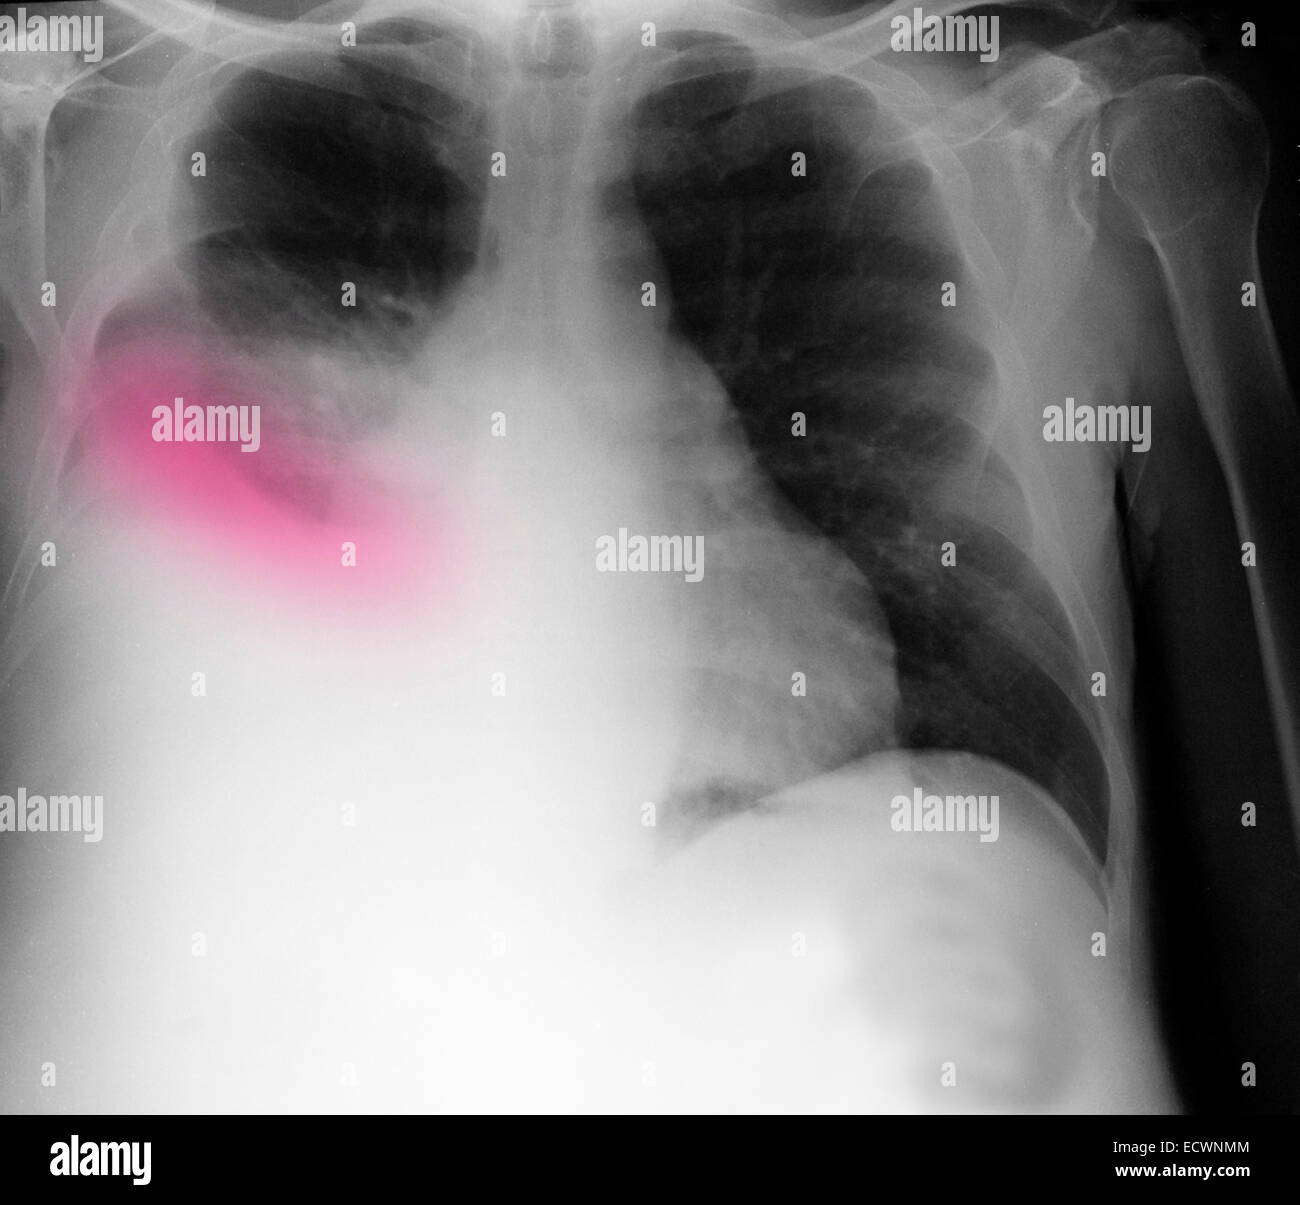

Chest X Ray Showing Pleural Effusion . Large amounts of fluid can. — pleural effusion is the buildup of excess fluid between the layers of the pleura around your lungs. — learn how to detect and diagnose pleural effusions using chest radiography, ct, ultrasound, and mri. See the signs of fluid accumulation, blunting of. — pleuritic chest pain due to a pleural effusion may disappear as fluid accumulates. — a comprehensive overview of pleural effusion, a condition where fluid collects between the lungs and the chest.

Chest X Ray Showing Right Pleural Effusion Download Scientific Diagram Chest X Ray Showing Pleural Effusion — learn how to detect and diagnose pleural effusions using chest radiography, ct, ultrasound, and mri. — pleural effusion is the buildup of excess fluid between the layers of the pleura around your lungs. See the signs of fluid accumulation, blunting of. — pleuritic chest pain due to a pleural effusion may disappear as fluid accumulates. . Chest X Ray Showing Pleural Effusion.

Chest Xray showing the massive pleural effusion on the right side that Chest X Ray Showing Pleural Effusion — pleuritic chest pain due to a pleural effusion may disappear as fluid accumulates. Large amounts of fluid can. See the signs of fluid accumulation, blunting of. — learn how to detect and diagnose pleural effusions using chest radiography, ct, ultrasound, and mri. — pleural effusion is the buildup of excess fluid between the layers of the. Chest X Ray Showing Pleural Effusion.